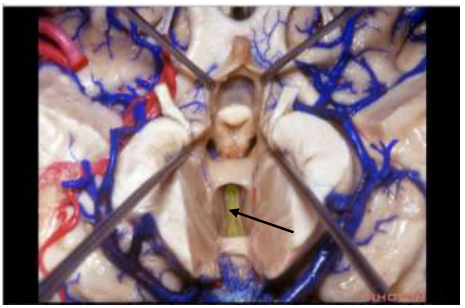

Neste corte sagital do cérebro, qual estrutura é apontada pela seta abaixo?

Neste corte transversal da fossa posterior craniana, qual estrutura é apontada pela seta abaixo?